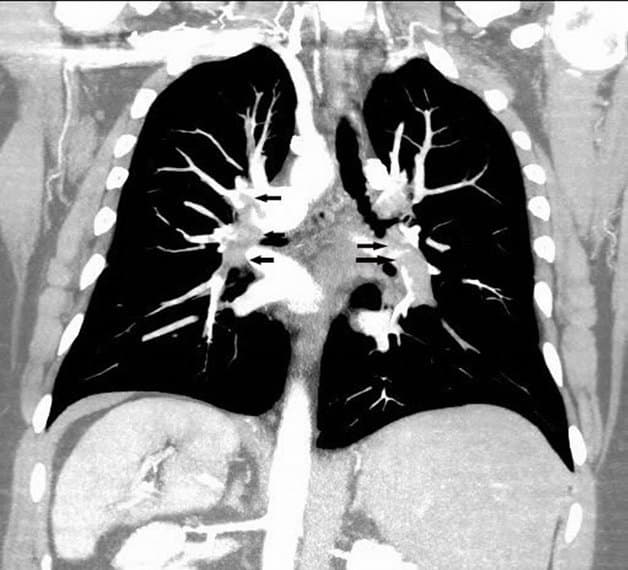

– Các bệnh lý về mạch máu như phình mạch, giả phình, dị dạng mạch máu, bóc tách động mạch, tắc hẹp, xơ vữa động mạch… Thì đều cần tiêm thuốc cản quang để chụp cắt lớp vi tính.

– Một số trường hợp đặc biệt cũng cần tiêm thuốc cản quang bao gồm: Tìm nguồn mạch nuôi phổi biệt lập, đánh giá vùng tưới máu của tổn thương, chẩn đoán mức độ vách hóa của tụ máu dưới màng cứng…